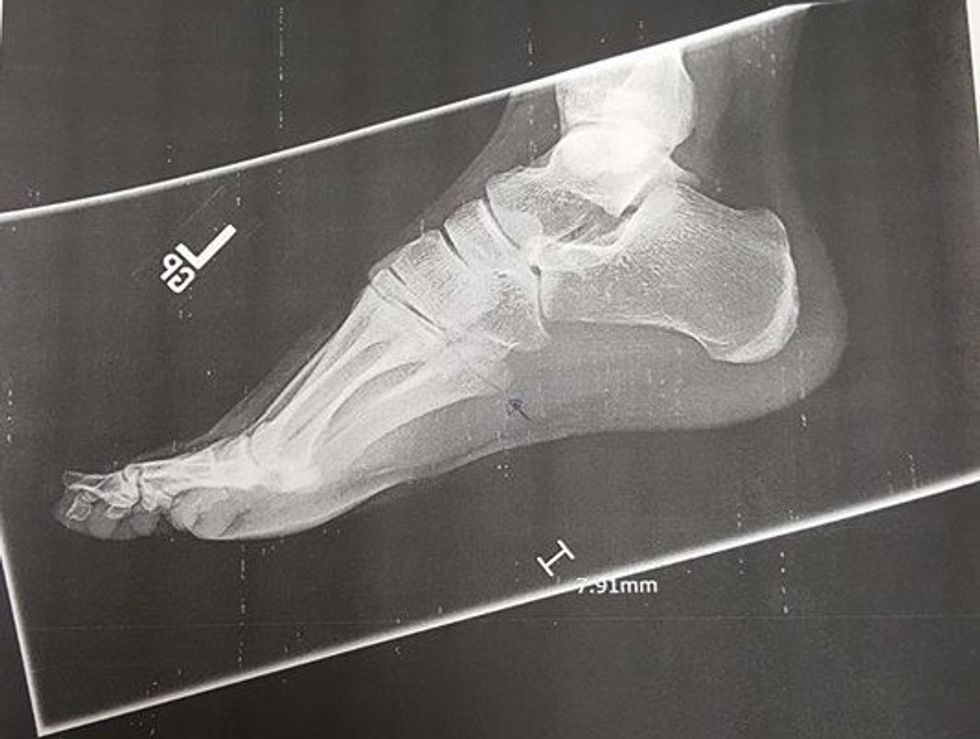

(If you want to see it, I've got my X-Ray picture attached down below this. If you're not, or don't like these things, probably don't scroll any further.)